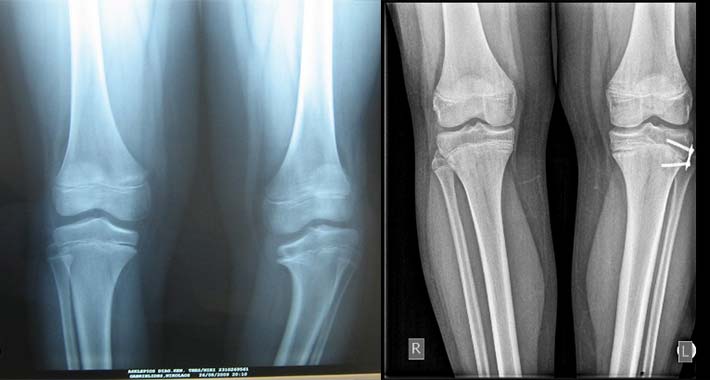

Εικόνα 4 Νόσος Blount, κλινική και ακτινολογική εικόνα ( Langeskiold 2)

Η ακτινολογική εικόνα εμφανίζει  καθίζηση του έσω τμήματος της άνω επίφυσης της κνήμης, με σχηματισμό άκανθας στην μετάφυση της κνήμης. Η πάθηση ταξινομείται ακτινολογικά σε στάδια, με τα κριτήρια του Langeskiold.